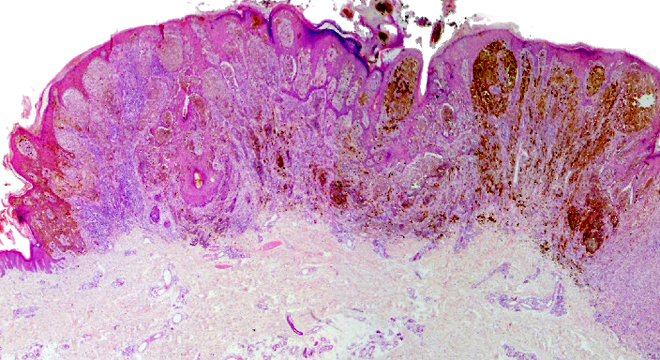

Es handelt sich um einen bösartigen, meist braunschwarz gefärbten Hautkrebs. Im Vergleich zu andern Hautkrebsarten verteilt er sich relativ früh durch Ableger (Metastasen) in andere Organe. Die Zahl der Menschen, die am schwarzen Hautkrebs erkranken, ist in den letzten Jahren gestiegen, obwohl er im Vergleich zu anderen Krebsarten (z.B. Lungen- Brust- oder Darmkrebs) doch eher selten ist. In der Schweiz zählt man ca. 2'400 Neuerkrankungen pro Jahr (Bundesamt für Statistik BSF, 2014) und rund 300 Personen sterben daran.

Gesichert ist, dass das Melanom von den Pigmentzellen der Oberhaut (auch aus gesunder Haut) ausgeht. Diese Pigmentzellen entarten und beginnen unkontrolliert zu wuchern. Sie bewegen sich ungebunden in der Haut, was die frühe Tendenz zu Ablegern (Metastasen) erklärt.

Erst bildet sich ein kleines, bräunlich-schwarzes Mal. Das Mal nimmt an Grösse zu. Es verändert sich in der Oberfläche, die rötlich-schwarz erscheint. Im späteren Stadium kann die rötlich-schwarze Oberfläche unregelmässig oder höckerig erscheinen. Die Umrandung ist häufig unscharf und fransig. Der schwarze Hautkrebs kann bei Verletzungen leicht zu bluten beginnen.

C - Color (Farbe): Verschiedene Farbtöne gleichzeitig sind verdächtig.